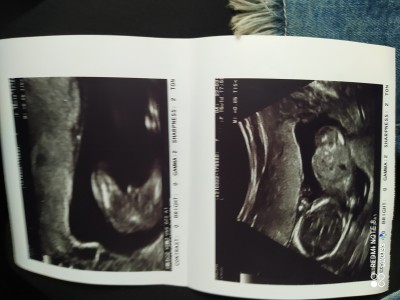

İlk olan resim 15 haftalık civarı ve doktorum %90 erkek dedi sonrasında şuan 20 hafta 3 günlüğüm başka bi özel doktorum da bugün ilk %90 kız dedi sonrasında ben erkek dendi bana dediğim zaman %90 erkek dedi kafamız çok aşırı karıştı. İkili resim olan ilk denilen teklisi bugünkü olan resim. Allah ne verirse kabulum ama artık biseyler yapmam lazım çocuk için ama doktorları çözemiyorum gitti :( Sizce nedir ne değildir anlamıyorum :((

Çıkıntı var erkek cnm

Alttaki resim 20 haftalık olanmiki

Evet bacım tekli olan 20 haftalık ikili olan 15 haftalik

Canım bizimde var 21 haftalık çok net bı resim bariz belli ultrasyon danmidir  nedir birinci resimden anlamadım bişey ikincide çıkıntı var ama bilemedim Rabbim gonlunuze göre versin inşallah